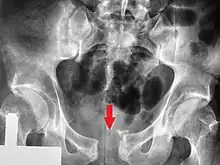

Post traumatic pubic symphysis diastasis

Separation of the symphysis pubis (diastasis)

An X-ray film obtained in the AP view of the pelvic inlet and outlet will show a marked gap between the pubic bones.[3] A normal pelvis will show a gap that is 4–5 mm. However, in pregnancy the hormonal influences cause relaxation of the connecting ligaments and the bones separate up to 9 mm. A gap measuring greater than 10 mm indicates a pathological process.[3]

In addition, a view in the "flamingo stance" can be obtained to demonstrate the instability of the joint. This position consists of the patient standing with weight on one leg and the other bent.[6] A vertical displacement of more than 1 cm is an indicator of symphysis pubis instability.[7] A displacement of more than 2 cm usually indicates involvement of the sacroiliac joints.[3]